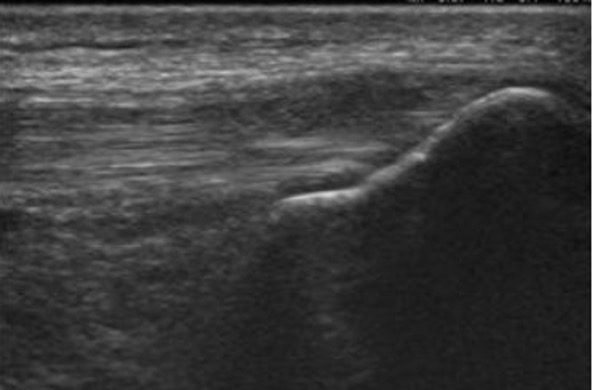

Let us look at some examples below of actual lesions which should not be confused with anisotropy artifact. Tendon tears, rupture or tendinopathy may appear like anisotropy. Transducer angulation or maneuvers such as heel-toe maneuver will not change the appearance of the lesion. Observe how they appear very similar to the anisotropy artifact.

Figure 4. B-mode image showing rupture of superficial part of the quadriceps tendon. This was not an anisotropy artifact. The hypoechoic lesion did not disappear by changing the angulation of the transducer to make the ultrasound beam perpendicular to the tendon fibers. Always correlate clinically and compare with the normal side.